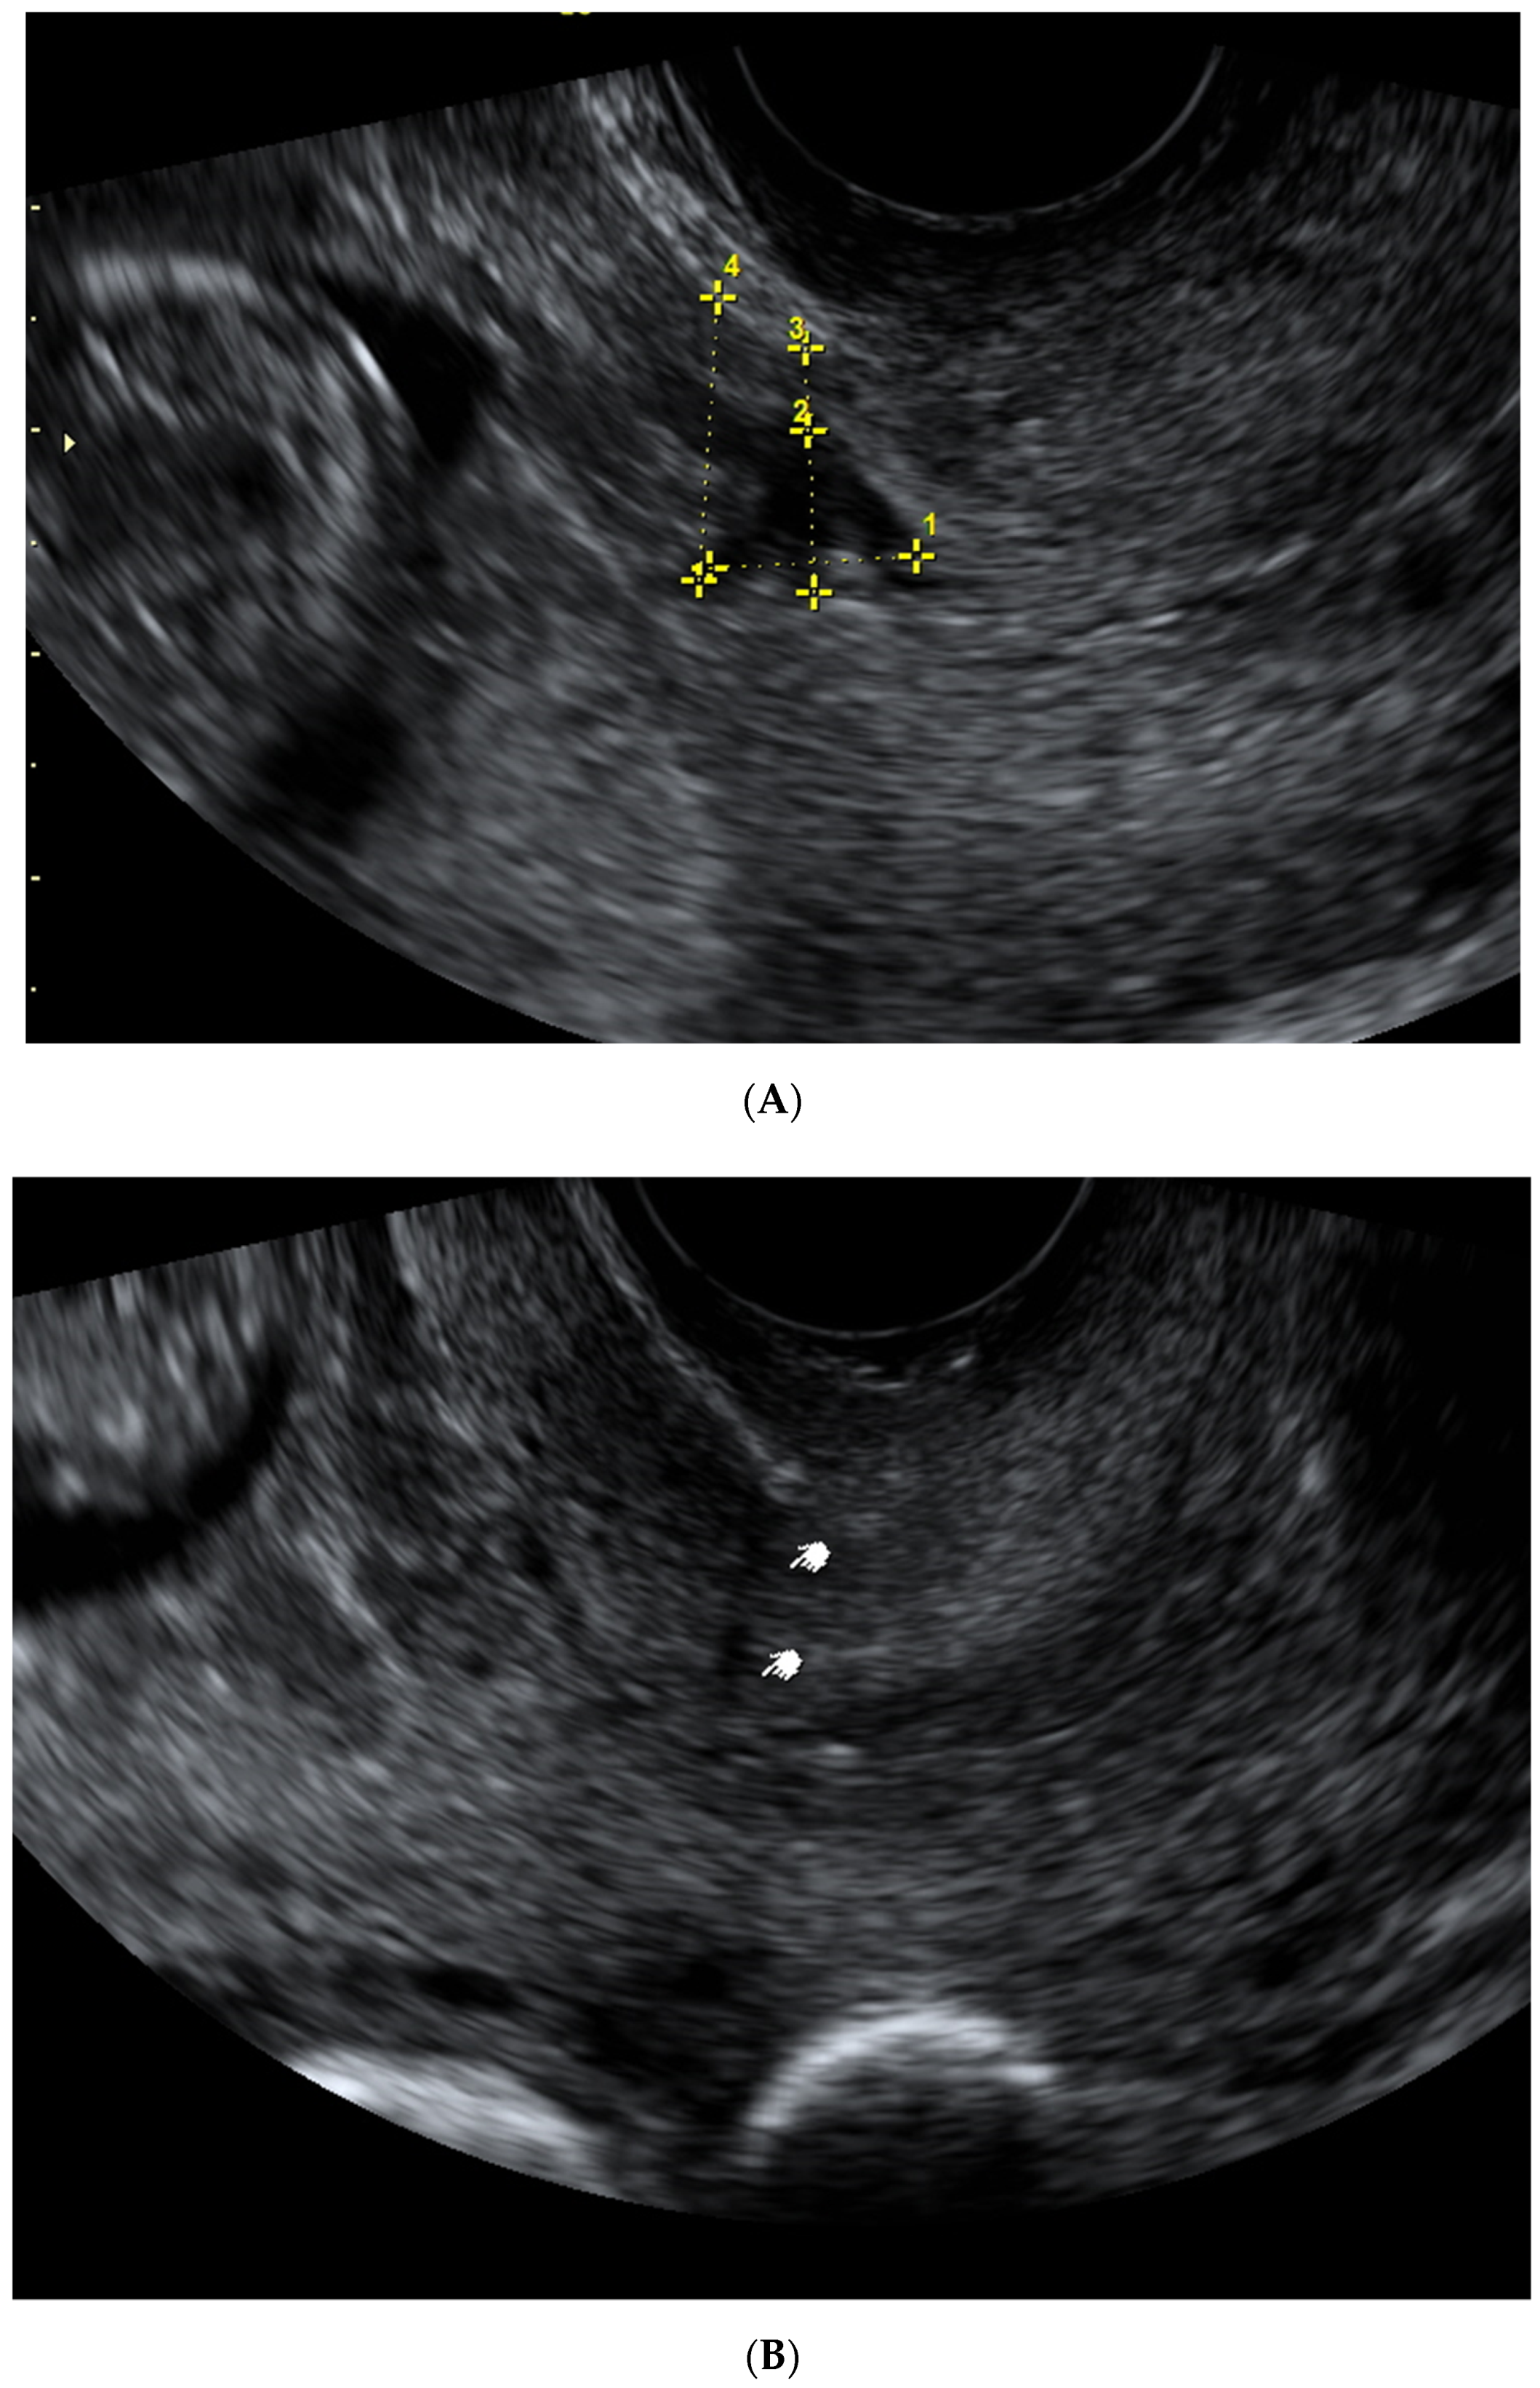

| Scar Characteristic (mm) | First Trimester Median (IQR)  | Second Trimester Median (IQR)  | Third Trimester Median (IQR)  |

|---|---|---|---|

| CS scar niche length | 5.0 (3.9–7.0) | - | - |

| CS scar niche depth | 6.9 (4.8–9.7) | - | - |

| RMT | 4.7 (3.3–5,9) | - | - |

| Myometrial thickness in the isthmus uteri | 12.7 (10.8–14.5) | - | - |